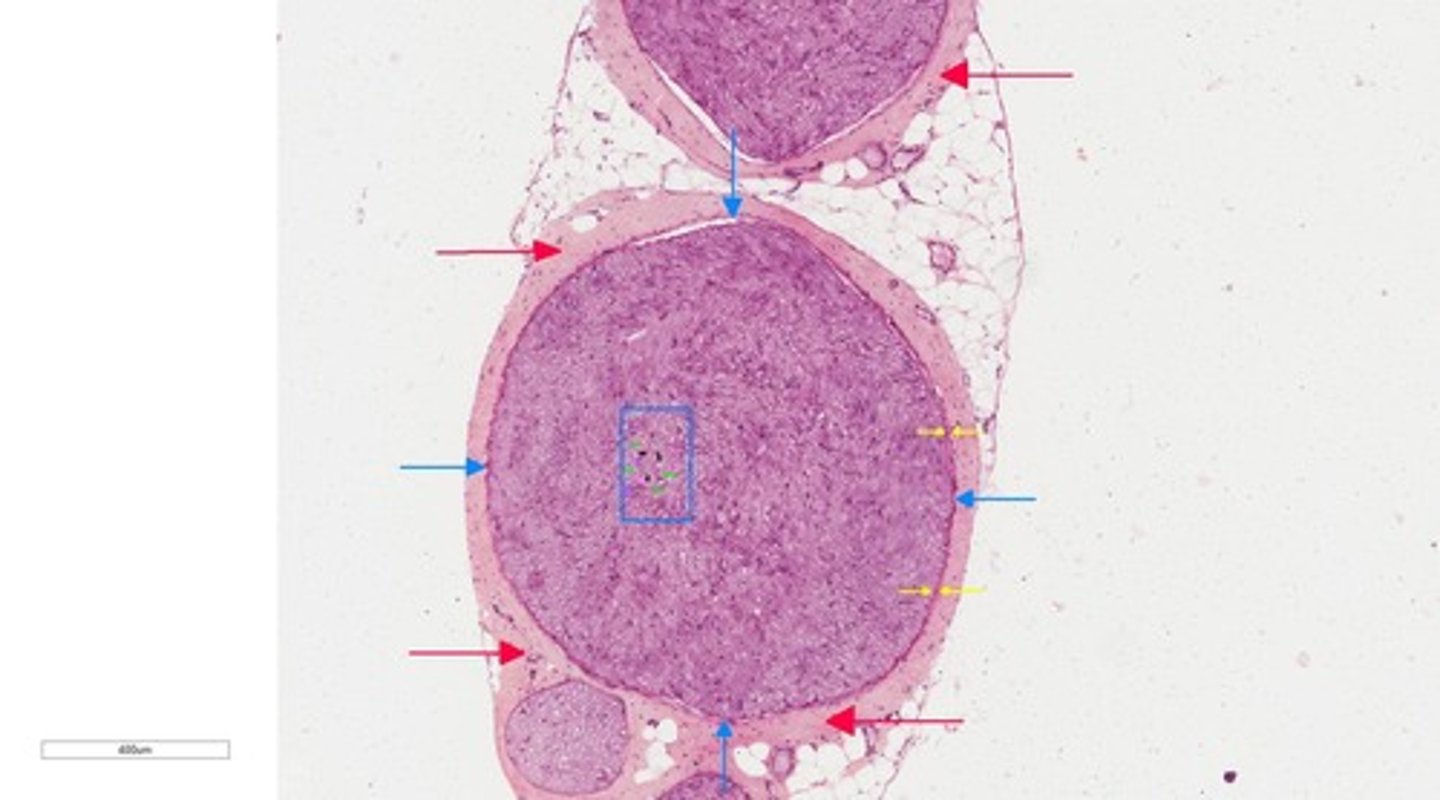

Epineurium

red arrow

fasicle

perineurium

blue arrow

Endoneurium

myelinated sheath

myelinated axon

axon/myelinated axon

2

myelin sheath gap

9

11